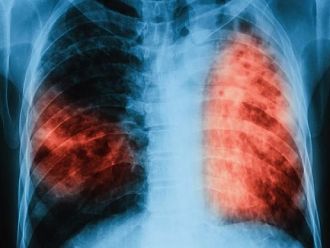

За последните 10 години в България e налице тенденция за намаляване заболяемостта от туберкулоза. Това съобщиха от Министерството на здравеопазването по повод Световния ден за борба с туберкулозата – 24 март, който тази година е под мотото „Време е – за свят без туберкулоза! Време е за действие!“

От 38,5 на 100 000 души население през 2008 г., през 2018 г. броят на лицата с туберкулоза вече е до 18,3 на 100 000 души население. Общият брой на регистрираните с туберкулоза лица през 2019 г. е 1 344, спрямо 1 358 за 2018 г. За сравнение, техният брой през 2008 г. е 3 150. Запазва се тенденцията броят на мъжете да е над два пъти по-голям от този на жените. Най-засегнати са възрастовите групи, както следва: от 35 до 44 г. (21%), над 65 г. (21%) и 55-64 г. (19%).

През 2019 г. се отчита значително намаляване на случаите на туберкулоза сред децата от 0 до 17 г. Регистрирани са 67 случая или 5% от всички случаи на туберкулоза в страната. През 2018 г. са регистрирани 90 деца с туберкулоза, а за сравнение, през 2008 г. техният брой е 282.

Въпреки намаляването на заболяемостта у нас, все още има региони, в които тя е над средната за страната. Такива са областите: Кюстендил – с 32,8 случая на 100 хил. души население, Враца – 33,2; Сливен – 28,4; Ямбол – 26,9; Габрово – 27,7; Смолян – 26,6; Перник – 25,6.